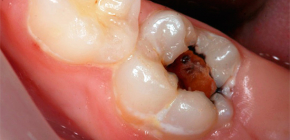

In termini semplici, la pulpite è un'infiammazione del "nervo" dentale (polpa), che fino ad allora era protetta in modo affidabile dalle pareti del dente, ma a causa di un graduale aumento della profondità della cavità, l'infezione è penetrata nella camera pulpare. Il nervo infiammato si gonfia, aumentando di volume e in aggiunta a ciò, può essere spremuto dall'essudato purulento.Insieme, tutto ciò porta spesso a un forte dolore, quando una persona letteralmente non riesce a trovare un posto, ed è costretto a iscriversi a un dentista per cure di emergenza.